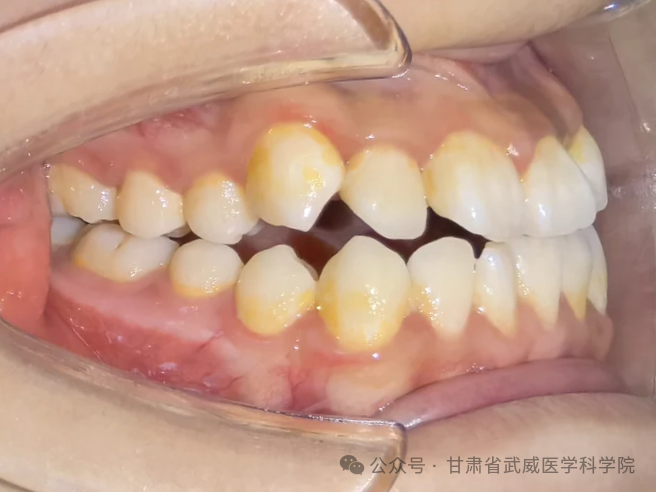

牙列不齐,医学上称为“错颌畸形”,是指儿童在生长发育过程中,由先天的遗传因素或后天的环境因素(如疾病、口腔不良习惯、替牙异常等)导致的牙齿、颌骨、颅面的畸形。

·异常磨损: 牙齿排列不齐会导致咬合力量分布不均,个别牙齿过度磨损,出现酸痛、敏感甚至断裂。

·“地包天”: 下牙包住上牙,会导致面中部凹陷,形成“月牙脸”。

·龅牙/小下巴: 上颌前突或下颌后缩,导致开唇露齿,嘴唇无法自然闭合。

·偏颌: 长期单侧咀嚼导致脸型不对称,变成“大小脸”。